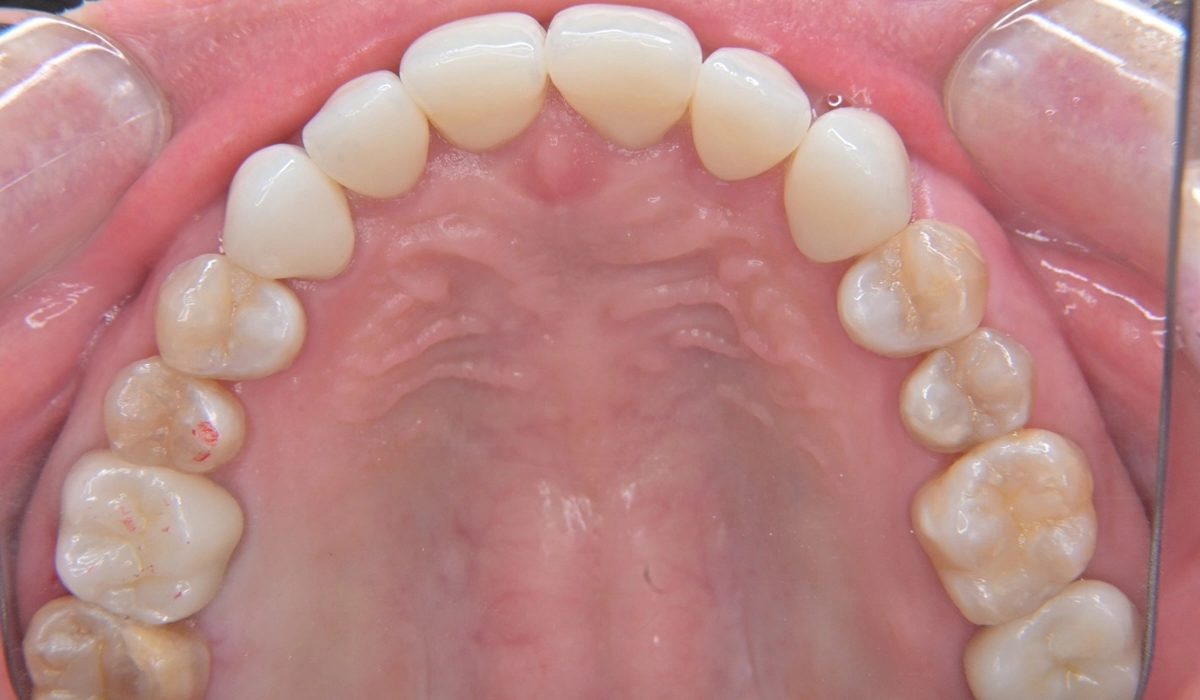

治療後の写真がこちらになります。

プロビジョナルレストレーションで問題点していたブラックトライアングルの問題が最終補綴物では修正できていることがわかります。

右上6と左下7はダイレクトボンディングにより必要最小限の切削介入で治療を行っています。右下6欠損部に対しては様々な治療選択肢のメリット・デメリットを考慮の上ジルコニアブリッジによる欠損修復治療を行いました。